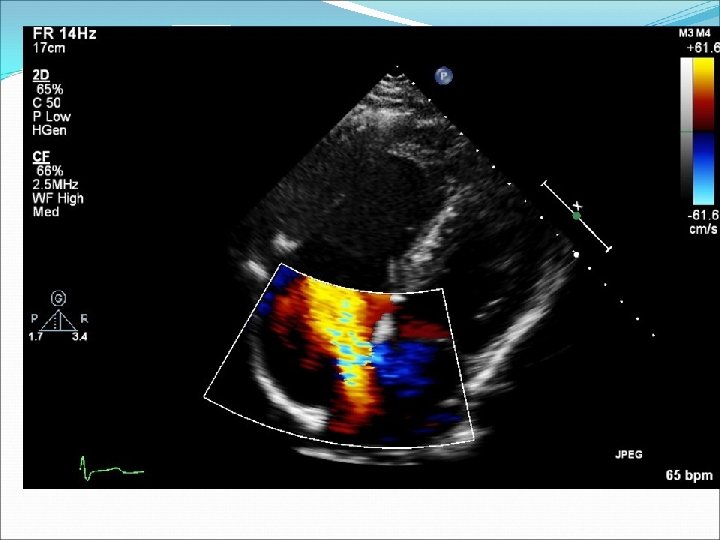

Defekt síňového septa: diagnostika echokardiografie, často jícnová: dilatovaná pravá komora zkratový proud barevným dopplerovským vyšetřením při přítomnosti trikuspidální regurgitace neinvazivně z rychlosti regurgitace odhadovat výši systolického tlaku v plicnici kalkulovat systémový průtok(Qs) ve výtokovém traktu levé komory a plicní průtok(Qp) v kmeni plicnice a počítat jejich poměr EKG: obraz bloku pravého raménka Tawarova u 95 % pacientů je projevem opožděné aktivace dilatované pravé komory Skiagram hrudníku : dilatace pravé komory, pravé síně, dilatace plicnice, zvýšenou plicní kresbu. Katetrizační vyšetření : před uzávěrem defektu u starších pacientů k posouzení plicní vaskulární rezistence a k provedení selektivní koronarografie.